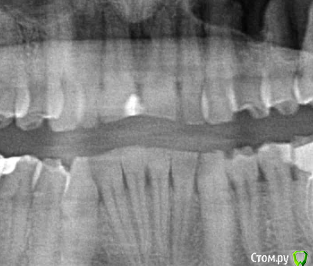

alex2016 Опубликовано 23 апреля, 2016 Поделиться Опубликовано 23 апреля, 2016 Добрый день, Сегодня был у стоматолога в профилактических целях. Т.к. нахожусь в США, то насчитали на ремонт 2600$ (учитывая страховку), т.к. 2600 тратить не сильно горю желанием хочу посоветоваться. Вопрос #1. В одном из зубов (его назвали №19 вроде как, снимок 1) врач обнаружил абсцесс. В этом зубе делали депульпирование и врач сказал, что депульпирование было сделано не до конца и на снимке это видно, т.е. они хотят заново вскрывать канал и заливать его (оба). К тому же он сказал, что в канале застрял кончик сверла (тут не уверен что это называется именно сверло) и его придётся доставать, возможно со стороны десны, если традиционным методом сделать это не получится. Абцесс он мне показал на снимке как небольшое затемнение на челюсти. Зуб не болит и кроме того, что между ним застряёт еда и он сам выглядит не презентабельно ничем не мешает, врач предлагает ставить коронку. Насчёт коронки возражений нету, т.к. еда застряёт и зуб выглядит не презентабельно, хотя в глаза это не бросается т.к. это моляр, а вот насчёт абсцесса я бы хотел уточнить здесь и получить второе мнение. Вопрос #2. Доктор предлагает поставить коронку на зубе #30, картинка #2. Хотя на зубе и достаточно большая пломба, он не выглядит не презентабельно и абсолютно не беспокоит, конечно, он выглядит чуть хуже обычного зуба, но гораздо лучше зуба #1. Сам я склоняюсь к тому, что пока с этим зубом делать ничег не нужно, но второе мнение хотелось бы всё-таки выслушать. Вопрос #3. Доктор предлагает удалить верхние зубы мудрости, т.к. они оказывают давление на дёсны или ещё куда-то там. Здесь я склоняюсь к тому, что он может быть прав насчёт верхнего зуба, потому что у меня там периодически застряёт еда между десной и самим зубом и вызывает неприятные ощущения, правый верхний зуб мудрости абсолютно никаких негативных ощущений не вызывает. Есть ли возможность избавиться от застрявания еды между зубом и десной (это происходит сзади-справа) без удаления зуба? Можно ли удалять один зуб мудрости, а не оба? Вопрос #4. У меня не правильный прикус из-за которого сточились передние верхние зубы, доктор предлагает удалить два верхних зуба, которые идут за клыками, подтянуть верхние передние зубы вперёд и поставить на них коронки, чтобы вернуть хороший прикус и эстетику (сейчас при закрытом рте расстояние между передними зубами верхней челюсти и нижней примерно в 1см). Вся эта процедура займёт кучу времени, т.к. придётся ставить брекет систему и удалять зубы. В клинике в Киеве мне тоже предлагали такой вариант. Зубы хочу сделать, чтобы улыбка стала красивее, поэтому вопросы: А. Обязательно ли удалять 2 зуба для этой процедуры?Б. Если удалить два верхних зуба мудрости, не отодвинутся ли зубы назад сами по себе?В. Хороший ли вариант ставить коронки на абсолютно здоровые, но немного сточенные зубы дли улучшения эстетики? Возможно зубы можно просто нарастить?Г. Не повлияет ли удаление двух зубов на положение верхней губы? При закрытом рте отклонений в прикусе особо не заметно. Благодарю за ответы. Ссылка на комментарий

DmitrySH Опубликовано 23 апреля, 2016 Поделиться Опубликовано 23 апреля, 2016 Вопрос 1.Да, ревизия каналов нужна, коронка нужна, инструмента не увидел на снимке, самое интересное срезано.. нужен снимок еще как минимум 5 мм ниже. Ссылка на комментарий

alex2016 Опубликовано 23 апреля, 2016 Автор Поделиться Опубликовано 23 апреля, 2016 (изменено) Вопрос 1.Да, ревизия каналов нужна, коронка нужна, инструмента не увидел на снимке, самое интересное срезано.. нужен снимок еще как минимум 5 мм ниже.Вот сделал скриншот с другой фотографии. Качество какое есть, если нужно могу спросить нет ли у них качества получше, такое впечатление что отсканировали в самом плохом качестве, т.к. то что они мне показывали выглядело более детализировано. вопрос 2.Может быть не коронку, но керамический оверлей очень кстати, и вкладку или пломбу на 5ый зуб перед ним и 5ый над ним.Благодарю. Доктор, почему-то не упоминал об этой возможности, рассказывал только про импланты и коронки. Уточню насчёт этого. 3 вопрос, скорее всего да, но не по снимку об этом рассуждатьДа в плане того, что можно удалять только один зуб, или то, что можно избавиться от проблемы без удаления зуба? Зуб не болит абсолютно и я даже не знал о том, что это зуб мудрости, просто когда я ем орехи или морковку и они попадают между десной и зубом, то десна воспаляется и вызывает неприятные ощущения, вот сейчас абсолютно нормально и зуб не достаёт совсем, но когда доктор смотрел этот зуб я отчётливо понял, что это именно то место, потому что он его немного зацепил своим прибором, т.е. какая-то проблема там есть, но неужели такая мелочь решается только методом удаления зуба? Изменено 23 апреля, 2016 пользователем alex2016 Ссылка на комментарий

DmitrySH Опубликовано 23 апреля, 2016 Поделиться Опубликовано 23 апреля, 2016 По таком снимку тоже наличие/отсутствие инородного тела в канале сложно определить, но факт что требуется лечение.Ваши верхние восьмые зубы не используются по назначению. Можете смело удалять, в функциональном аспекте ничего не потеряете. 1 Ссылка на комментарий